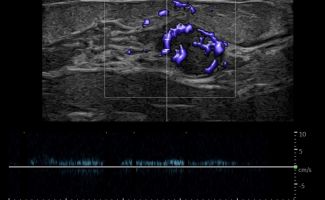

Modern ultrasound machines, equipped with advanced high-frequency transducers, techniques such as Color Doppler, Power Doppler, B-Flow, and Elastography, allow the analysis of breast architecture with exceptional accuracy.

Elastography can highlight the elasticity of a lesion, indicating whether it is hard or soft. Through this technique, we can assess the nature of the lesion, providing indications of whether it is benign or malignant. Additionally, with the contribution of Color Power Doppler and B-Flow, we can monitor the vascular flow within the lesions, offering even more information about the type and nature of the abnormality.